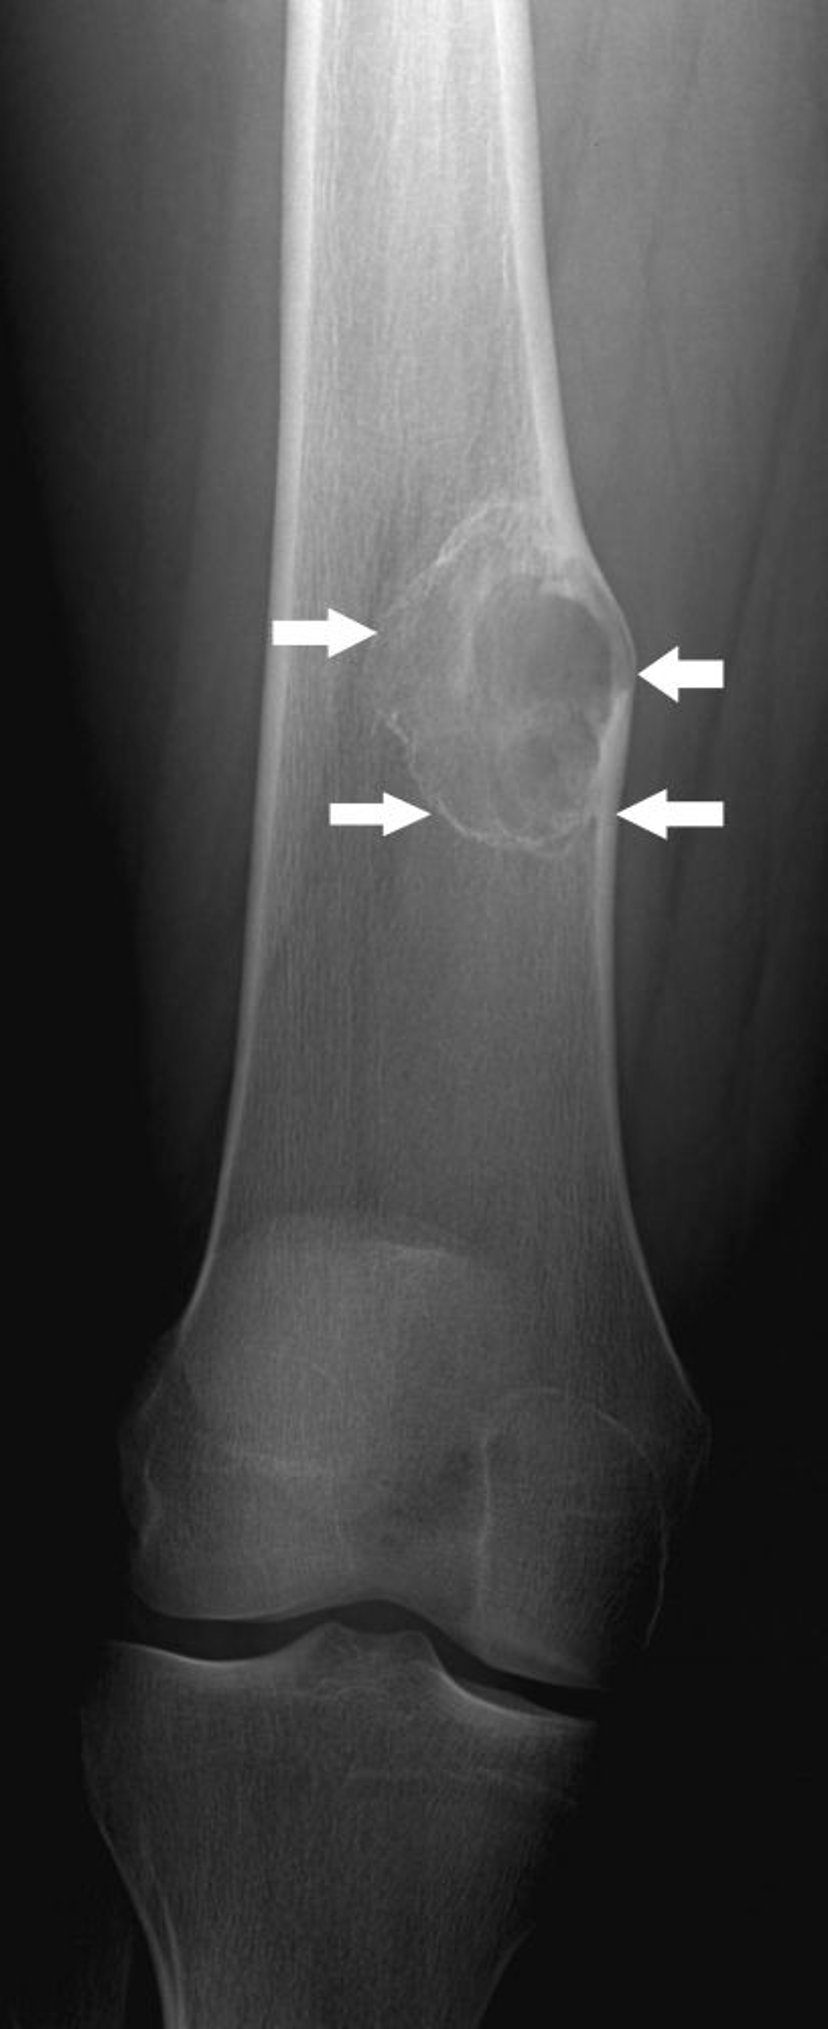

Fibroma não ossificante

Essa radiografia mostra lesão óssea (setas) acima do joelho no fêmur com expansão leve, típica do fibroma não ossificante.

Imagem cedida por cortesia de Michael J. Joyce, MD, and Hakan Ilaslan, MD.